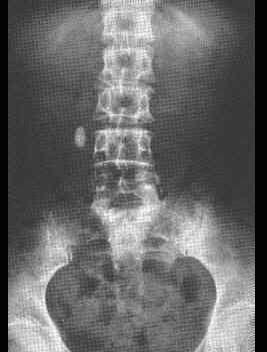

男,25岁,乘车后突然发生右下腹痛,伴恶心,近年来有同样发作史、查体:腹软,右下腹有深腹痛、血常规白细胞9×10/L、尿镜检:红细胞(+++),白细胞06...

问题 男,25岁,乘车后突然发生右下腹痛,伴恶心,近年来有同样发作史、查体:腹软,右下腹有深腹痛、血常规白细胞9×10/L、尿镜检:红细胞(+++),白细胞06个,应诊断为 ( )

选项 A、单纯不完全性肠梗阻 B、右侧输尿管结石 C、美克尔憩室炎 D、右侧输卵管炎 E、慢性阑尾炎急性发作

答案 B